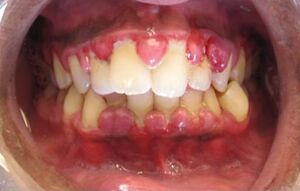

حالة التهاب لثة حادة.